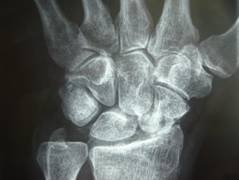

Radiografia delle mani destra e sinistra Riduzione della rima articolare metacarpofalangea (freccia) del terzo raggio della mano destra piccole erosioni nelle articolazioni interfalangee distali della mano destra (freccia) e prossimali della mano sinistra (freccia) Conservato il trofismo osseo Download Download fullsize image;. Sono stati arruolati i pazienti con ciascun sottotipo di artrite psoriasica, compresa artrite poliarticolare senza noduli reumatoidi (43%), artrite periferica asimmetrica (30%), artrite delle articolazioni interfalangee distali (DIP) (15%), spondilite con artrite periferica (11%) e artrite mutilante (1%). Falangi più distali Nelle dita possono essere identificati due tipi di articolaizoni interfalangee le articolazioni tra le falangi prossimale e media, dette articolazioni.